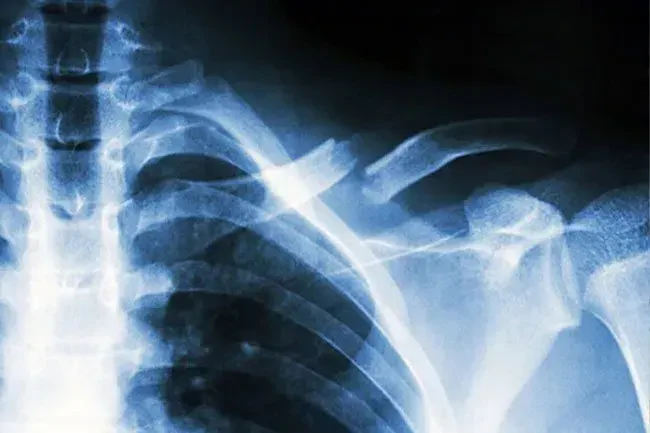

Nødhjælpssituationer: Hvad sker der, når du bryder en knogle

Hvilken slags pause?

Læger taler om knækkede knogler, der også kaldes brud med et par grundlæggende udtryk:

• Åben eller lukket? Lukkede eller enkle brud bryder ikke gennem huden. Åbne eller sammensatte dem gør.

• Delvis eller komplet? Delvise pauser går ikke hele vejen gennem knoglen. Komplette pauser betyder, at knoglen er i to eller flere stykker.

• Fordrevet eller ikke-forskudt? Hvis de ødelagte stykker stadig stiller op, er det en ikke-forskudt pause. Hvis de ikke gør det, er det forskudt.

Typer brud

Almindelige typer pauser inkluderer:

• Tværgående: bryder lige over knoglen

• Stressfraktur: En meget tynd revne kaldet også en hårgrænsefraktur

• Skrå: bryder i en vinkel

• Greenstick: Bryder på den ene side, men bøjer sig på den anden-som en frisk pind fra et træ

• Begyndt: knogler bryder i tre eller flere stykker

Andre typer inkluderer kompressionsfrakturer, der ofte sker i rygsøjlen spiralfrakturer og avulsionsfrakturer, når en sen eller ledbånd trækker et stykke knogler af.